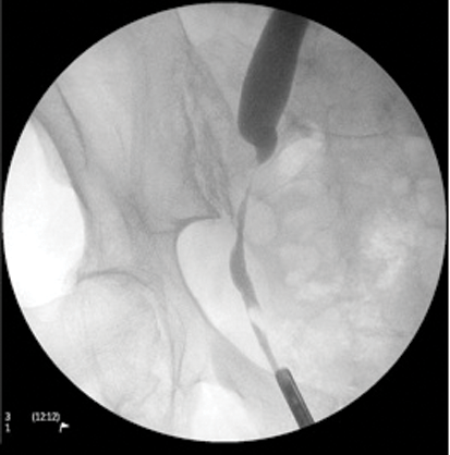

Case 1

- What is this investigation? What are the findings of this investigation?

-

Retrograde ureterogram. A narrowing of the right ureter at the pelvic brim with proximal ureteric dilatation. An air bubble can also be seen within the lower ureter.